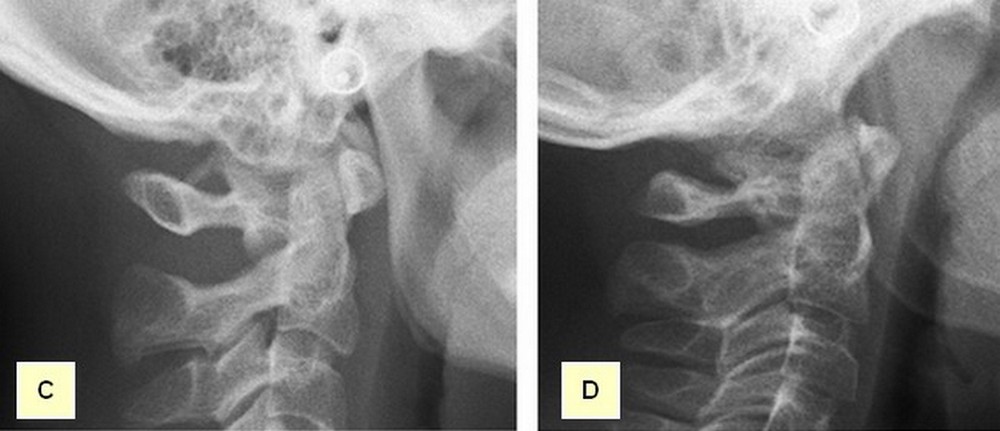

Despite the fact that this calcification has been associated with different painful disorders, some other authors consider it an anatomical condition destined to protect the vertebral artery and not a pathological condition (8). PP is visible on lateral cervical spine and cranial lateral radiographs as thin bony arch on the shape of a ring crossing from the retroglenoid tubercle to the posterior arch of C1, being either partially of fully calcified (Figures C and D).

Figure C: Complete PP shown on a lateral radiographic view. Figure D: Partial PP shown on a lateral radiographic view.